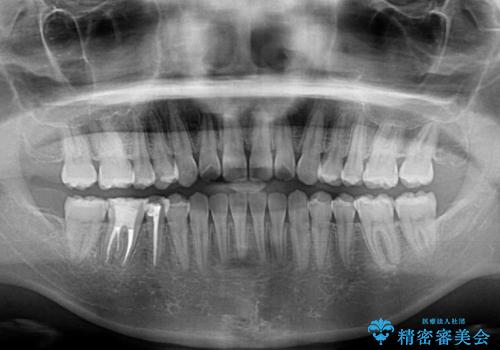

インビザラインによる反対咬合の改善は、上の歯が下の歯を乗り越えていく期間に咬み合わせが非常に不安定となり、治療が長期化することがあります。

こちらの患者様も、一時的に前歯でしか咬めない時期がありましたが、比較的早く咬み合わせが安定し、1年ほどで治療を終えることができました。